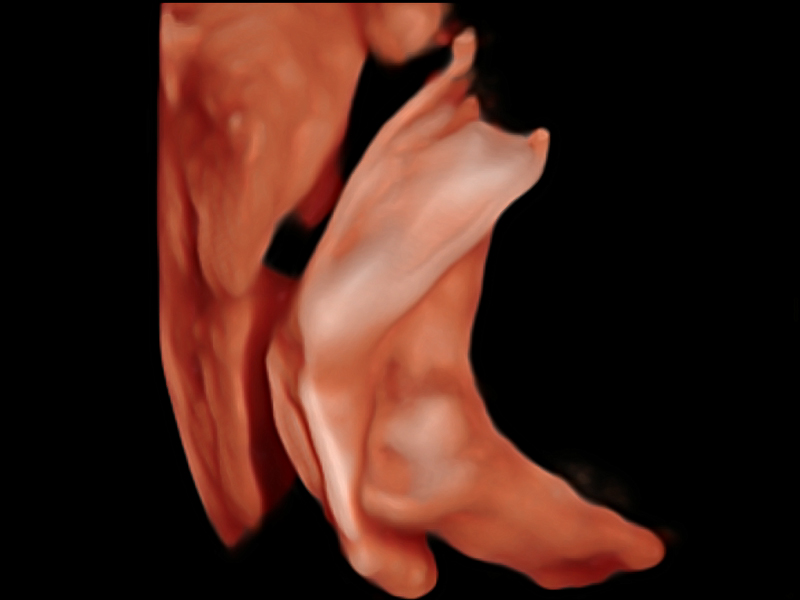

高分辨率血流成像技术提高了对低速血流信号的检测能力。在提高空间分辨率的同时,也克服了血流外溢现象,为用户提供更加真实的血流动力学信息。